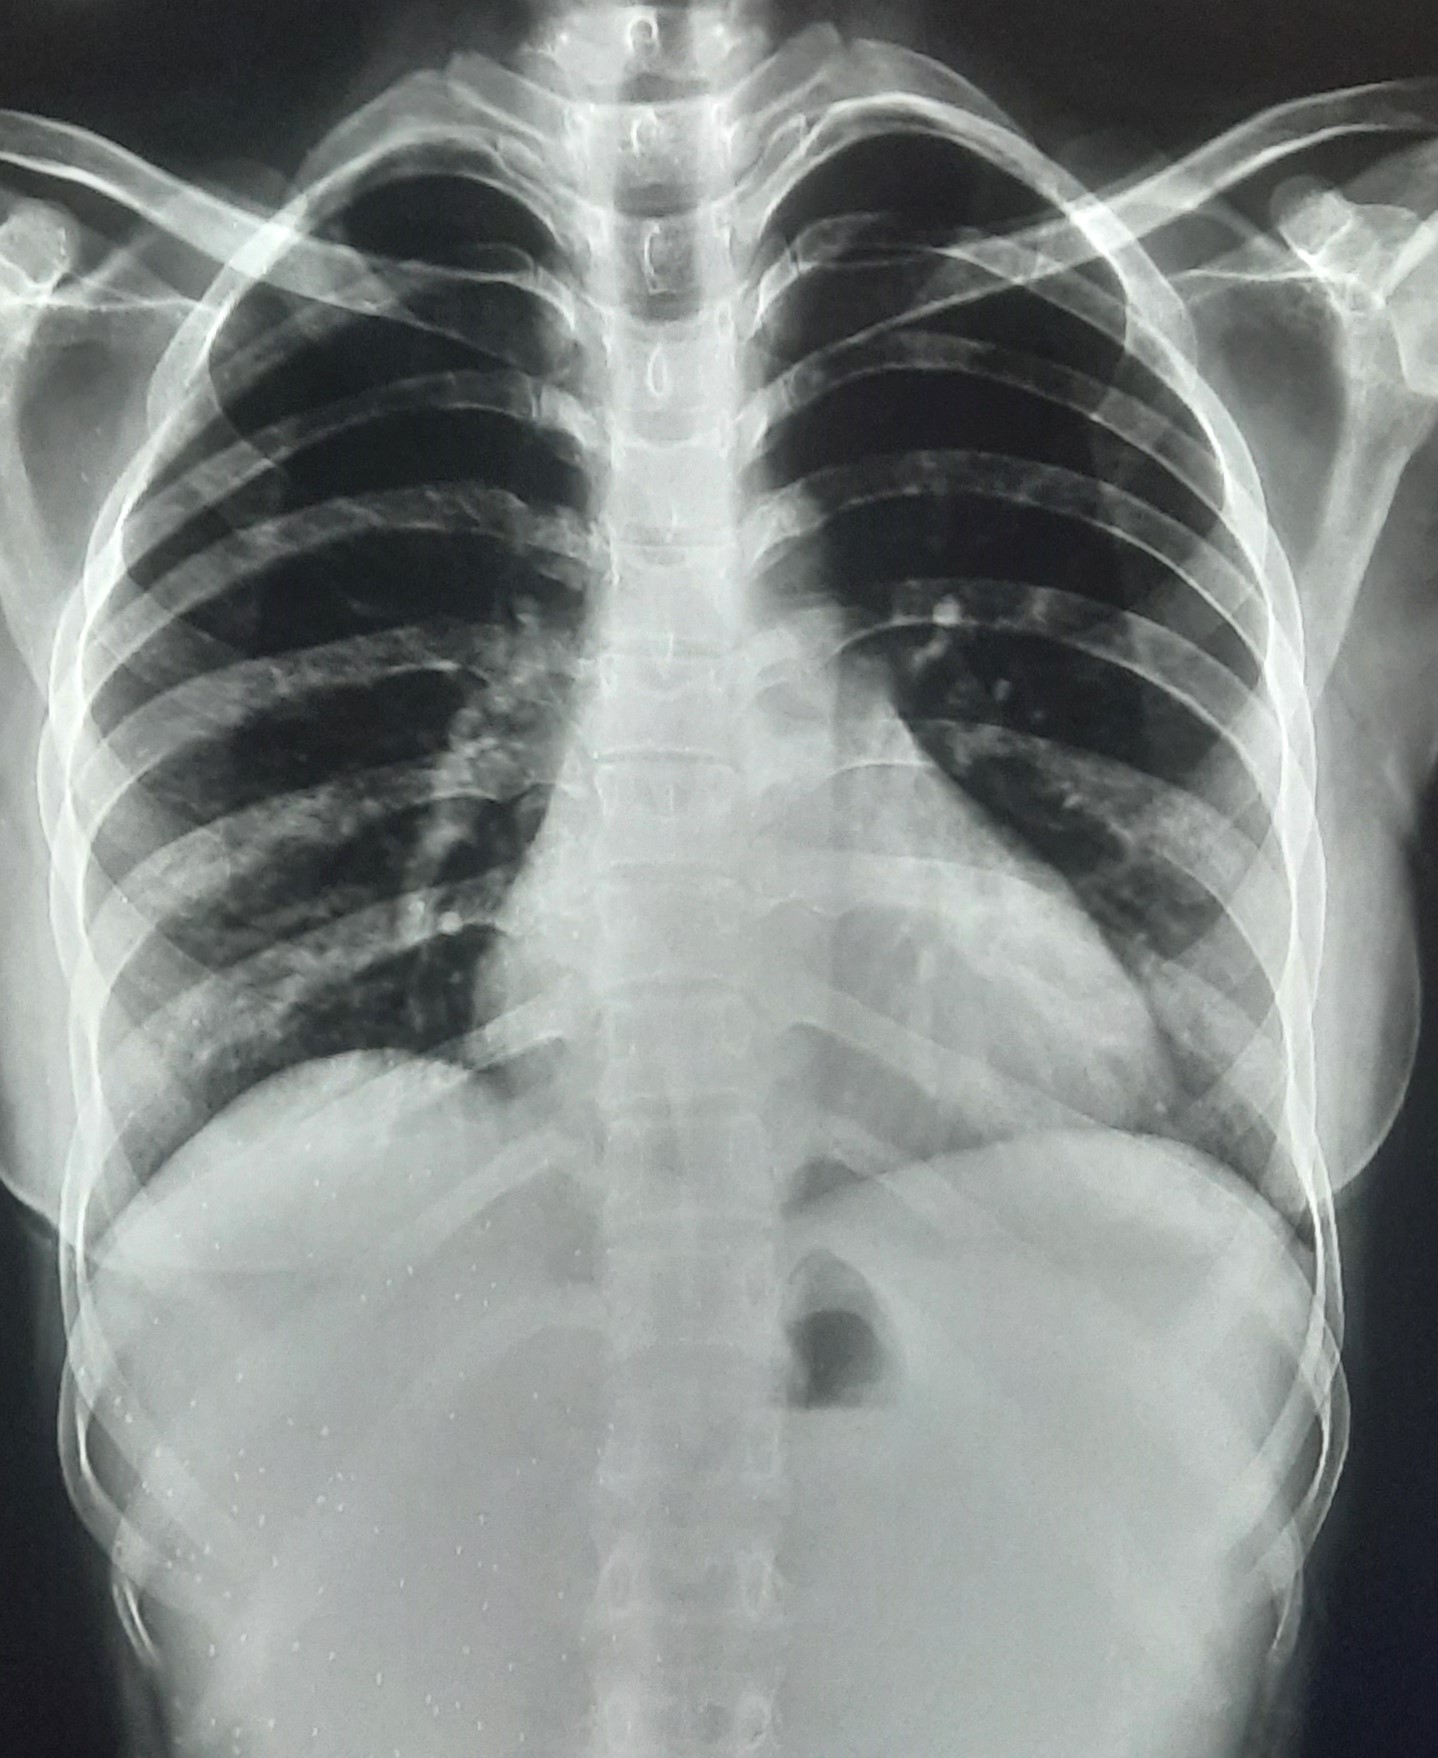

| 262 | IGGMC, Nagpur, Nagpur | P2 | 29-4210 | Mohamad Aslam | Consent taken on Paper | 35 Yrs. |

Provisional Diag : C/O Extra Pulmonary TB

Final Diag : FIBROSIS |

TB Case (Confirmed) | S/O RETICULAR OPACITIES NOTED IN RIGHT UPPER & MIDDLE ZONE/ QUERY FIBROSIS | Abnormality visible on x-ray |